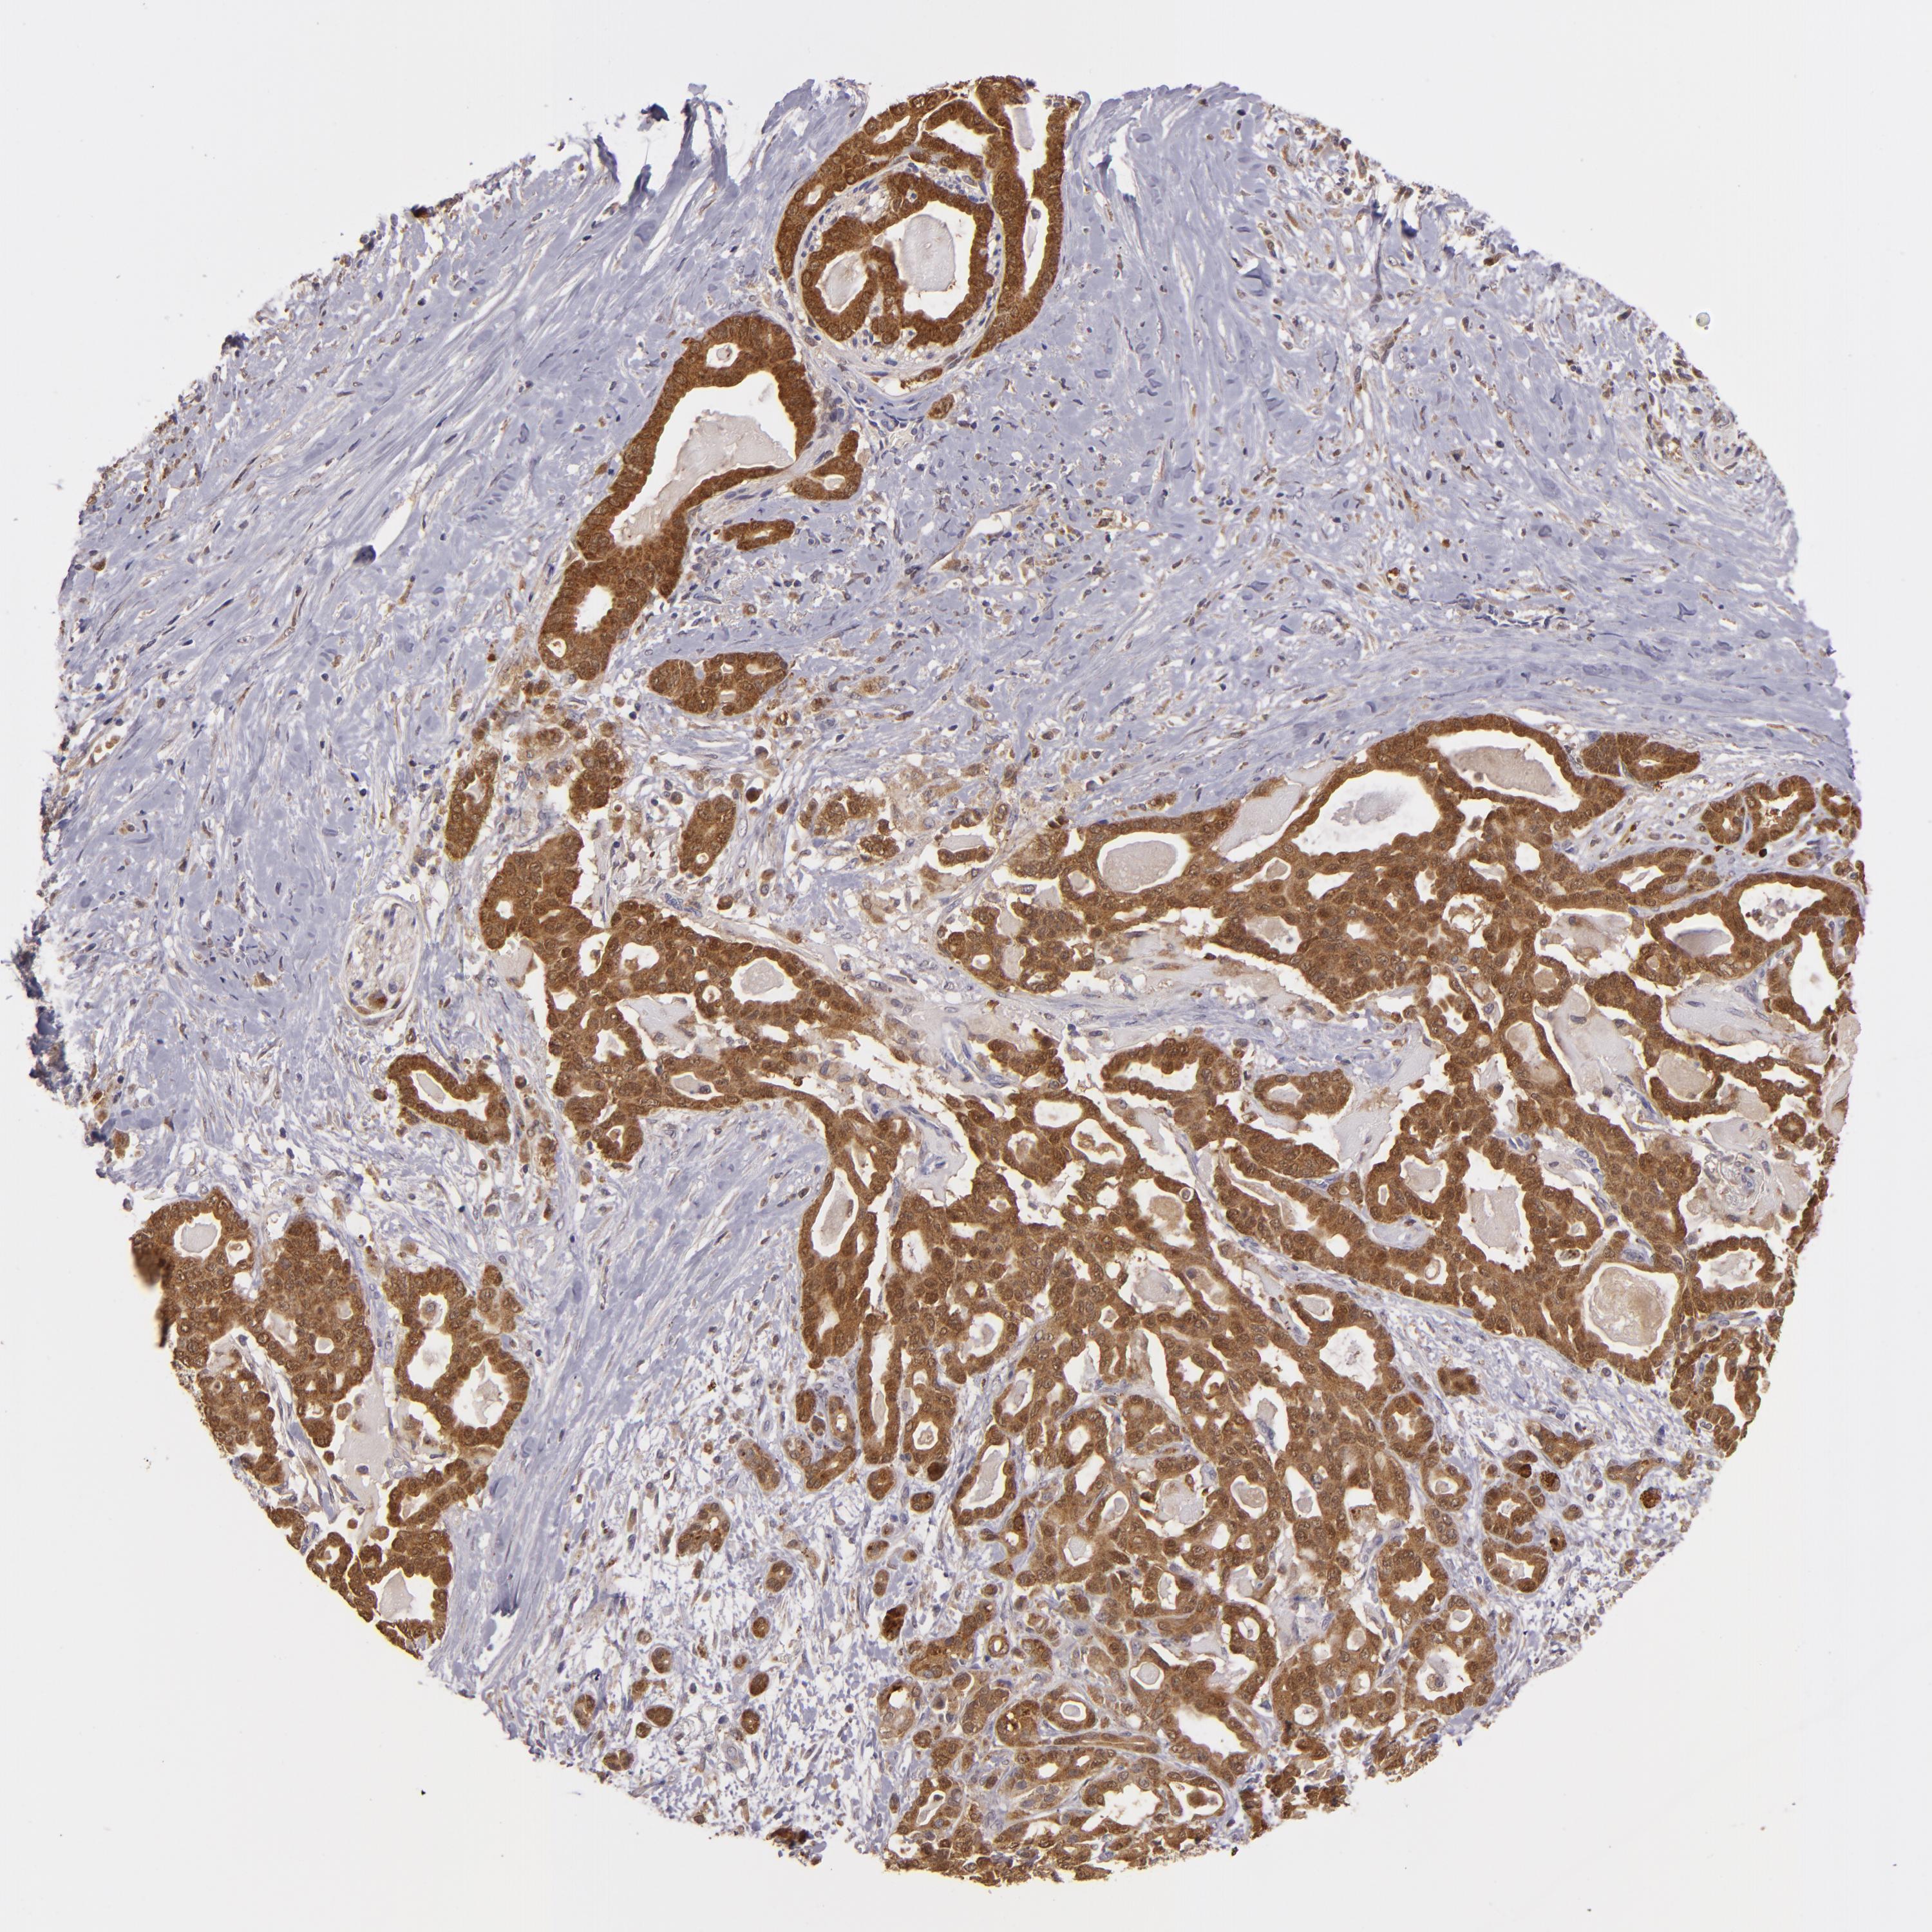

PANCREATIC CANCER - Protein expressioni

A mouse-over function shows sample information and annotation data. Click on an image to view it in a full screen mode. Samples can be filtered based on level of antibody staining by selecting one or several of the following categories: high, medium, low and not detected. The assay and annotation is described here.

Note that samples used for immunohistochemistry by the Human Protein Atlas do not correspond to samples in the TCGA dataset.

Antibody stainingi

Antibody staining in the annotated cell types in the current human tissue is reported as not detected, low, medium, or high, based on conventional immunohistochemistry profiling in selected tissues. This score is based on the combination of the staining intensity and fraction of stained cells.

Each image is clickable and will lead to virtual microscopy that enables deeper exploration of all samples and also displays staining intensity scores, fraction scores and subcellular localization as well as patient and tissue information for each sample.

Antibody HPA018840

Antibody HPA018909

Antibody CAB002684

Staining

High

Medium

Low

Not detected

Intensity

Strong

Moderate

Weak

Negative

Quantity

>75%

75%-25%

<25%

None

Location

Nuclear

Cytoplasmic/membranous

Cytoplasmic/membranous,nuclear

Adenocarcinoma, NOS

Adenocarcinoma, metastatic, NOS